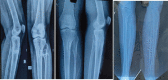

Case report: We have included five cases of osteochondromas occurring at rare locations with variable presentations and their management. We have included one case of metacarpal, one case of skull exostosis, two cases of scapula exostosis, and one case of fibula exostosis.